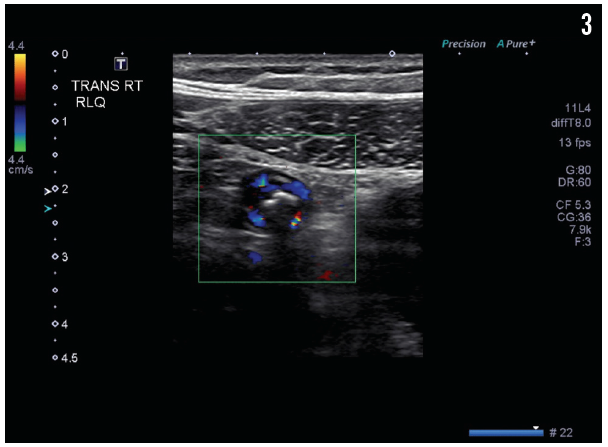

The results of pelvic ultrasonography (Figure 1) showed an elongate, tubular, noncompressible bowel loop in the right lower quadrant, measuring 8 mm, likely representing the appendix with a blind end, and suggesting acute appendicitis with appendicolith but without evidence of perforation. A cross-sectional scan (Figure 2) showed no free fluid or periappendicular fluid collection that would suggest perforation; it also demonstrated the “ring of fire” due to the high vascularity of the inflamed appendix (Figure 3).

Figure 3. A cross-sectional scan showed a tubular structure—the appendix with appendicolith. The high vascularity of the inflamed appendix creates a “ring of fire” appearance on cross-sectional ultrasonography images.